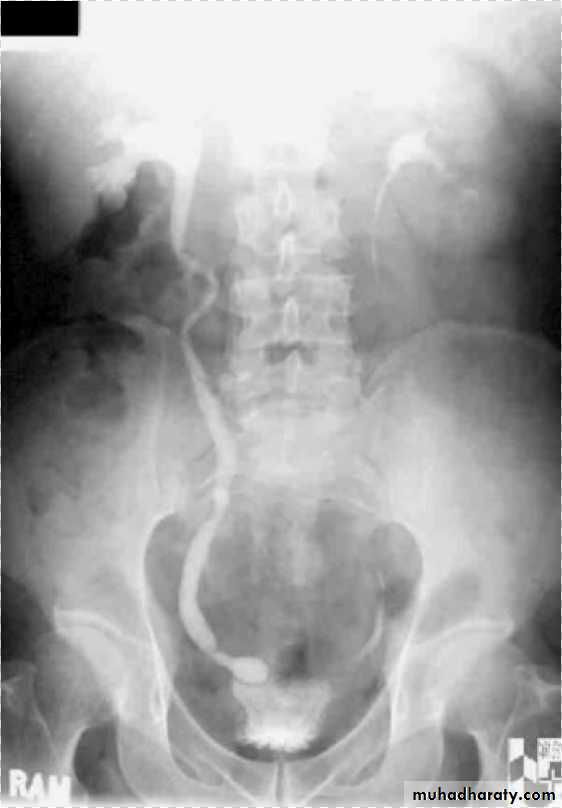

*Right kideny is ectopic(presacrally located)&bilateral hydronephrosis.

*Hydronephrosis&ectopic kidney